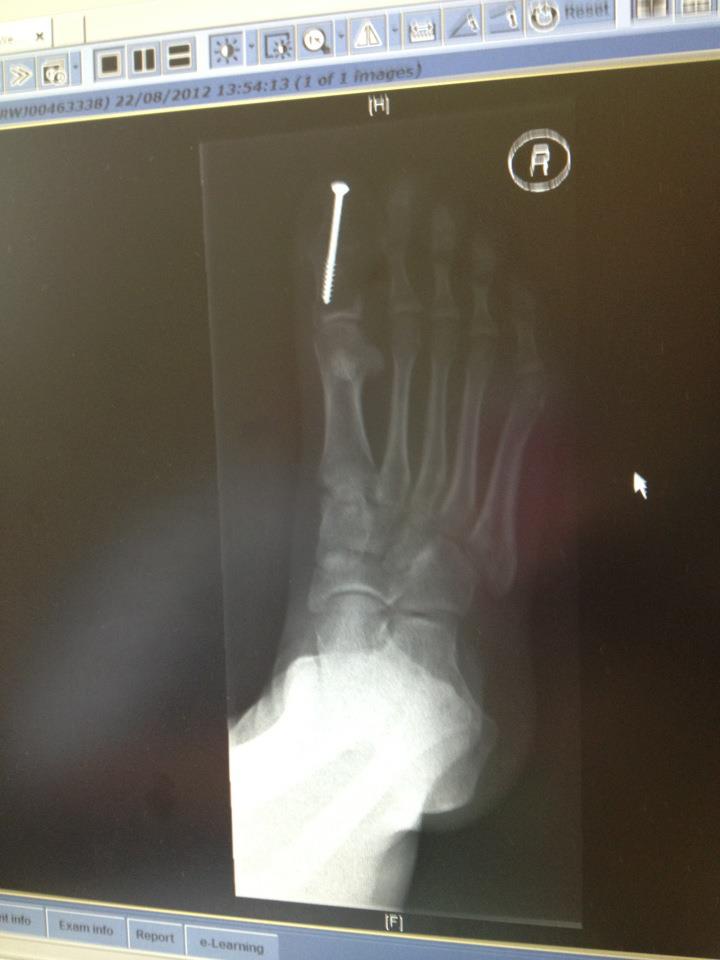

Running With Toe Fusion . Hallux limitus means the ‘stiff big toe’. A big toe fusion is performed as a definitive procedure to treat painful hallux rigidus (big toe arthritis) or sometimes for severe bunions. Just a update to say i have been running over 4 mile 3 times a week with no problems. Removal of joint surfaces preserves the joint while. Find out how in this article. Big toe fusion surgery is often recommended for patients suffering from big toearthritis and severe bunions. Though small, it can become a major factor that can hamper your running performance. The invasive procedure is extremely helpful in correcting toe malformation and reducing pain in the metatarsophalangeal joint. The two usual procedures are joint fusion and removal of joint surfaces. Hit 6 months since op tomorrow and. Big toe arthritis (also known as hallux rigidus) can cause pain and swelling and lead to difficulty. A first mtp joint fusion is a surgical procedure to treat arthritis of the big toe.

from londonfootandankle.co.uk

TOE FUSION SURGERY London Foot and Ankle